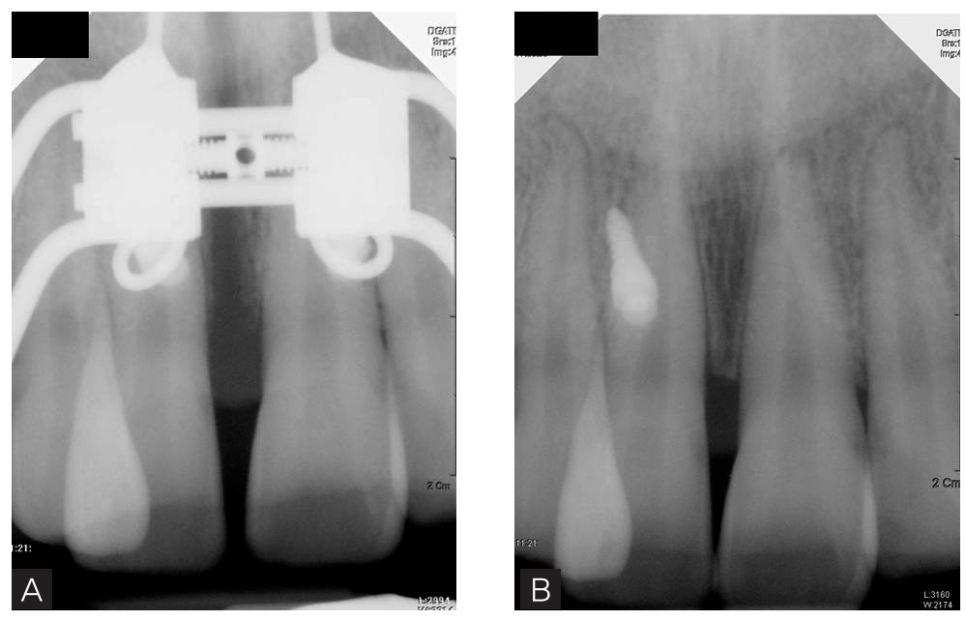

1. 최대확장량 및 속도 상하악 어금니가 어긋나지 않을 정도까지 가능한 최대한으로 넓혀주는 것이 좋습니다. 추후 경사진 어금니를 바로 세우기 위해 여유 있게 확.장합니다. 급속확장과 완속확장 방법이 있으며 나이가 어린 경우와 미니스크류를 이용한 경우에는 느리게 넓혀주는 것을 추천합니다. 특히 미니스크류를 식립하여 정중구개봉합 (입천장 정중앙에 뼈가 결합된 부위)을 분리하기 위해 하루에 1회 돌리는 것을 추천하며 2회 이상 확.장을 시도하는 경우, 뼈 부위의 압력 증가로 환자가 통증을 호소할 수 있습니다. 혼합치열기 어린이에서는 주로 가철식 장치로 확.장하는데 5일 혹은 일주일에 1회 돌리는 완속방법을 시행하며 청소년에서는 미니스크류를 식립하지 않은 경우에는 하루에 1회 혹은 2회, 미니스크류를 식립한 경우에는 하루에 1회 돌리는 방법을 사용하고 있습니다. 골성 확장이 일어나면 앞니가 벌어지는 현상이 나타나며 치근단 방사선 사진에서 봉합의 이개(뼈가 분리되어 벌어짐)가 관찰됩니다. 2. miniscrew 식립 개수 2개인 경우와 4개인 경우, 응력분포에 차이를 보이며 성인에서는 골질의 견고성을 감안하여 4개의 치아와 4개의 골내고정원(미니스크류)을 포함하는 것이 응력의 분산에 도움이 됩니다. 골이 덜 단단한 청소년에서는 2개만 식립하기도 합니다. 3. 악궁 확장 시 발생할 수 있는 현상과 유지 기간 상악궁을 넓히는 동안 상악의 어금니가 전보다 협측(밖)으로 이동하므로 구치부 교합에서 일시적인 개방교합이 대부분 발생하게 되고, 이는 구치의 협설측 경사도의 개선으로 곧 소실됩니다. 오히려 부적절한 횡적 교합관계 (상하악 구치부 폭경이 맞지 않음)를 방치하면 상악의 어금니가 하악의 어금니를 적절하게 덮지 못하게 되고 이는 확장이 없으면 개선하기 어렵게 됩니다. 또한 가운데 봉합부위가 벌어지면 앞니도 벌어지게 되는 데 일반적으로 3개월 정도의 유지기간을 거치면 분리된 부분에 새로운 뼈가 형성이 되고, 이를 확인한 후 장치를 제거하게 됩니다.